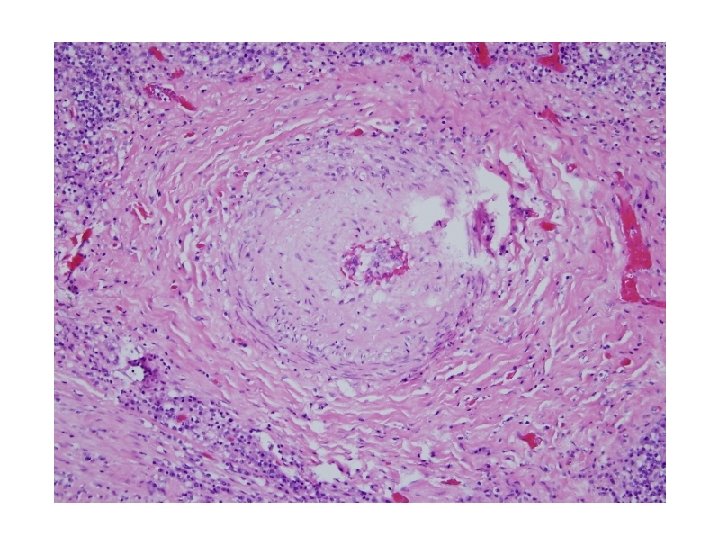

Patient Follow-up • Given granulomas and acid fast bacilli, sputum was sent for culture. Three sputum samples were negative for acid fast bacilli. A ppd was placed and was also negative. • Patient was treated empirically with IRPE for four months.